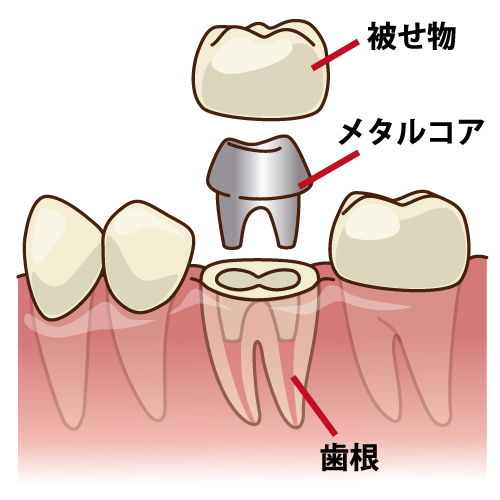

※メタルコアとは保険治療で最も一般的に使用されている金属の土台のことです。

通常、根の治療が終了すると、歯冠部を失ってしまった歯の根を補強するためにコアと呼ばれる土台を入れます。

クラウンのコアに使用される材料には、次のようなものがあります。

・メタル(銀合金)

・金合金

・ファイバー(グラスファイバーとコンポジットレジン)

メタルコアは強度があること、保険が適応されるなことなどから多く使用されていますが、デメットが多々ありますので注意が必要です。

食事の時の咬合圧、食いしばり、寝ているときの歯ぎしりなど、歯には毎日あらゆる方向からとても強い力がかかっています。メタルコアは歯よりも硬いため、強い力によって歯の根が割れてしまうことがあります。

食事の時の咬合圧、食いしばり、寝ているときの歯ぎしりなど、歯には毎日あらゆる方向からとても強い力がかかっています。メタルコアは歯よりも硬いため、強い力によって歯の根が割れてしまうことがあります。

また上に被せものをしても表面から金属の色が透けてみえたり、長く使い続けていくと、上記の通り金属の成分が溶出して歯茎を黒ずませるメタルタトゥーという審美性の問題が生じます。他にも金属アレルギーの原因となったり、ファイバーコアと比較して切削する歯質の量が明らかに多いため、歯の寿命を縮めてしまう可能性があります。